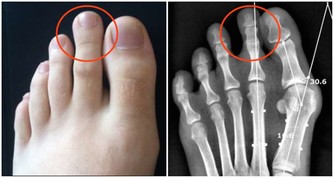

▼原來這個症狀被稱做「乾性溺水」,當水快吸進肺部時,身體會出現保護機制,

造成喉痙攣,導致呼吸能力受影響及昏迷、疲憊、咳嗽及胸口疼痛等。